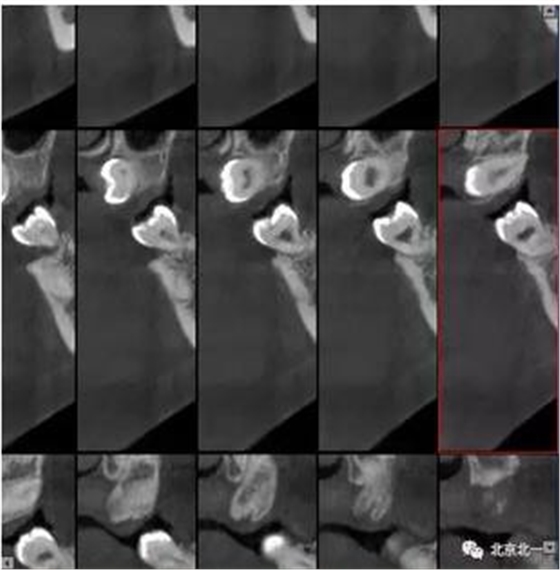

圖三:橫斷面可見智齒水平橫向腭側(cè)。完全骨埋伏。

圖四:冠狀面截圖牙根位于唇側(cè),牙冠位于腭側(cè)。

圖五:矢狀位截圖可見牙冠截面。